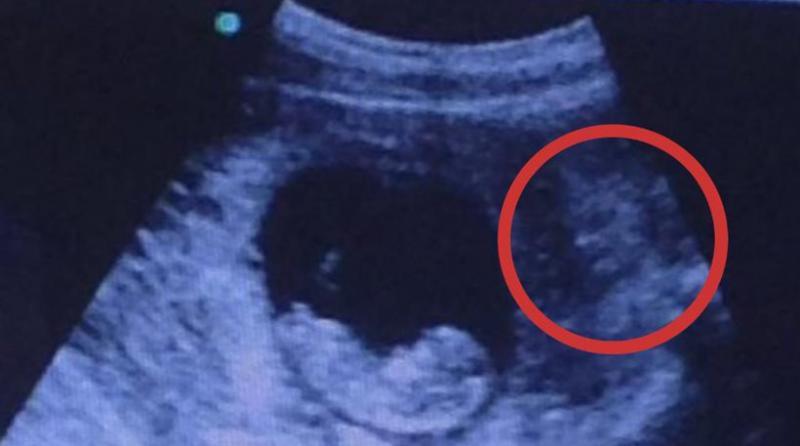

«Οι γονείς πήγαν στο γιατρό για να δουν πώς είναι το μωράκι τους και βρέθηκαν μπροστά σε μια δυσάρεστη έκπληξη» αναφέρει η εφημερίδα ενώ ο τίτλος του ρεπορτάζ της είναι:

«Σοκαριστικό υπερηχογράφημα αποκαλύπτει την παρουσία “δαίμονα” δίπλα σε αθώο μωρό»,

Η φωτογραφία του υπερηχογραφήματος, έχει γίνει ήδη viral. Δείτε την.